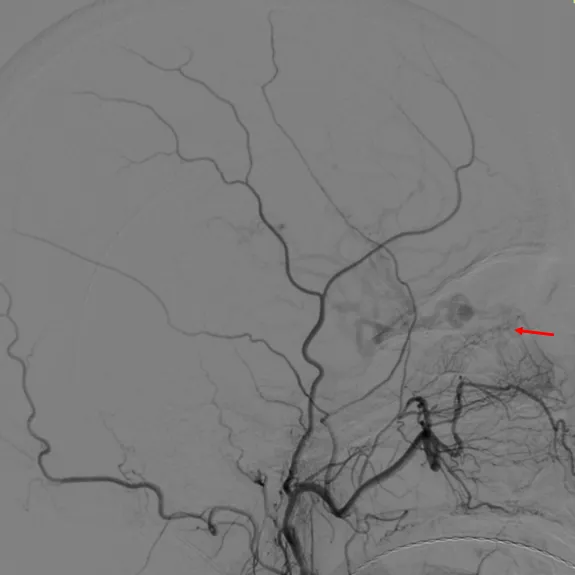

术前造影

右颈内造影

左颈内造影

右颈外无异常

左颈外无异常